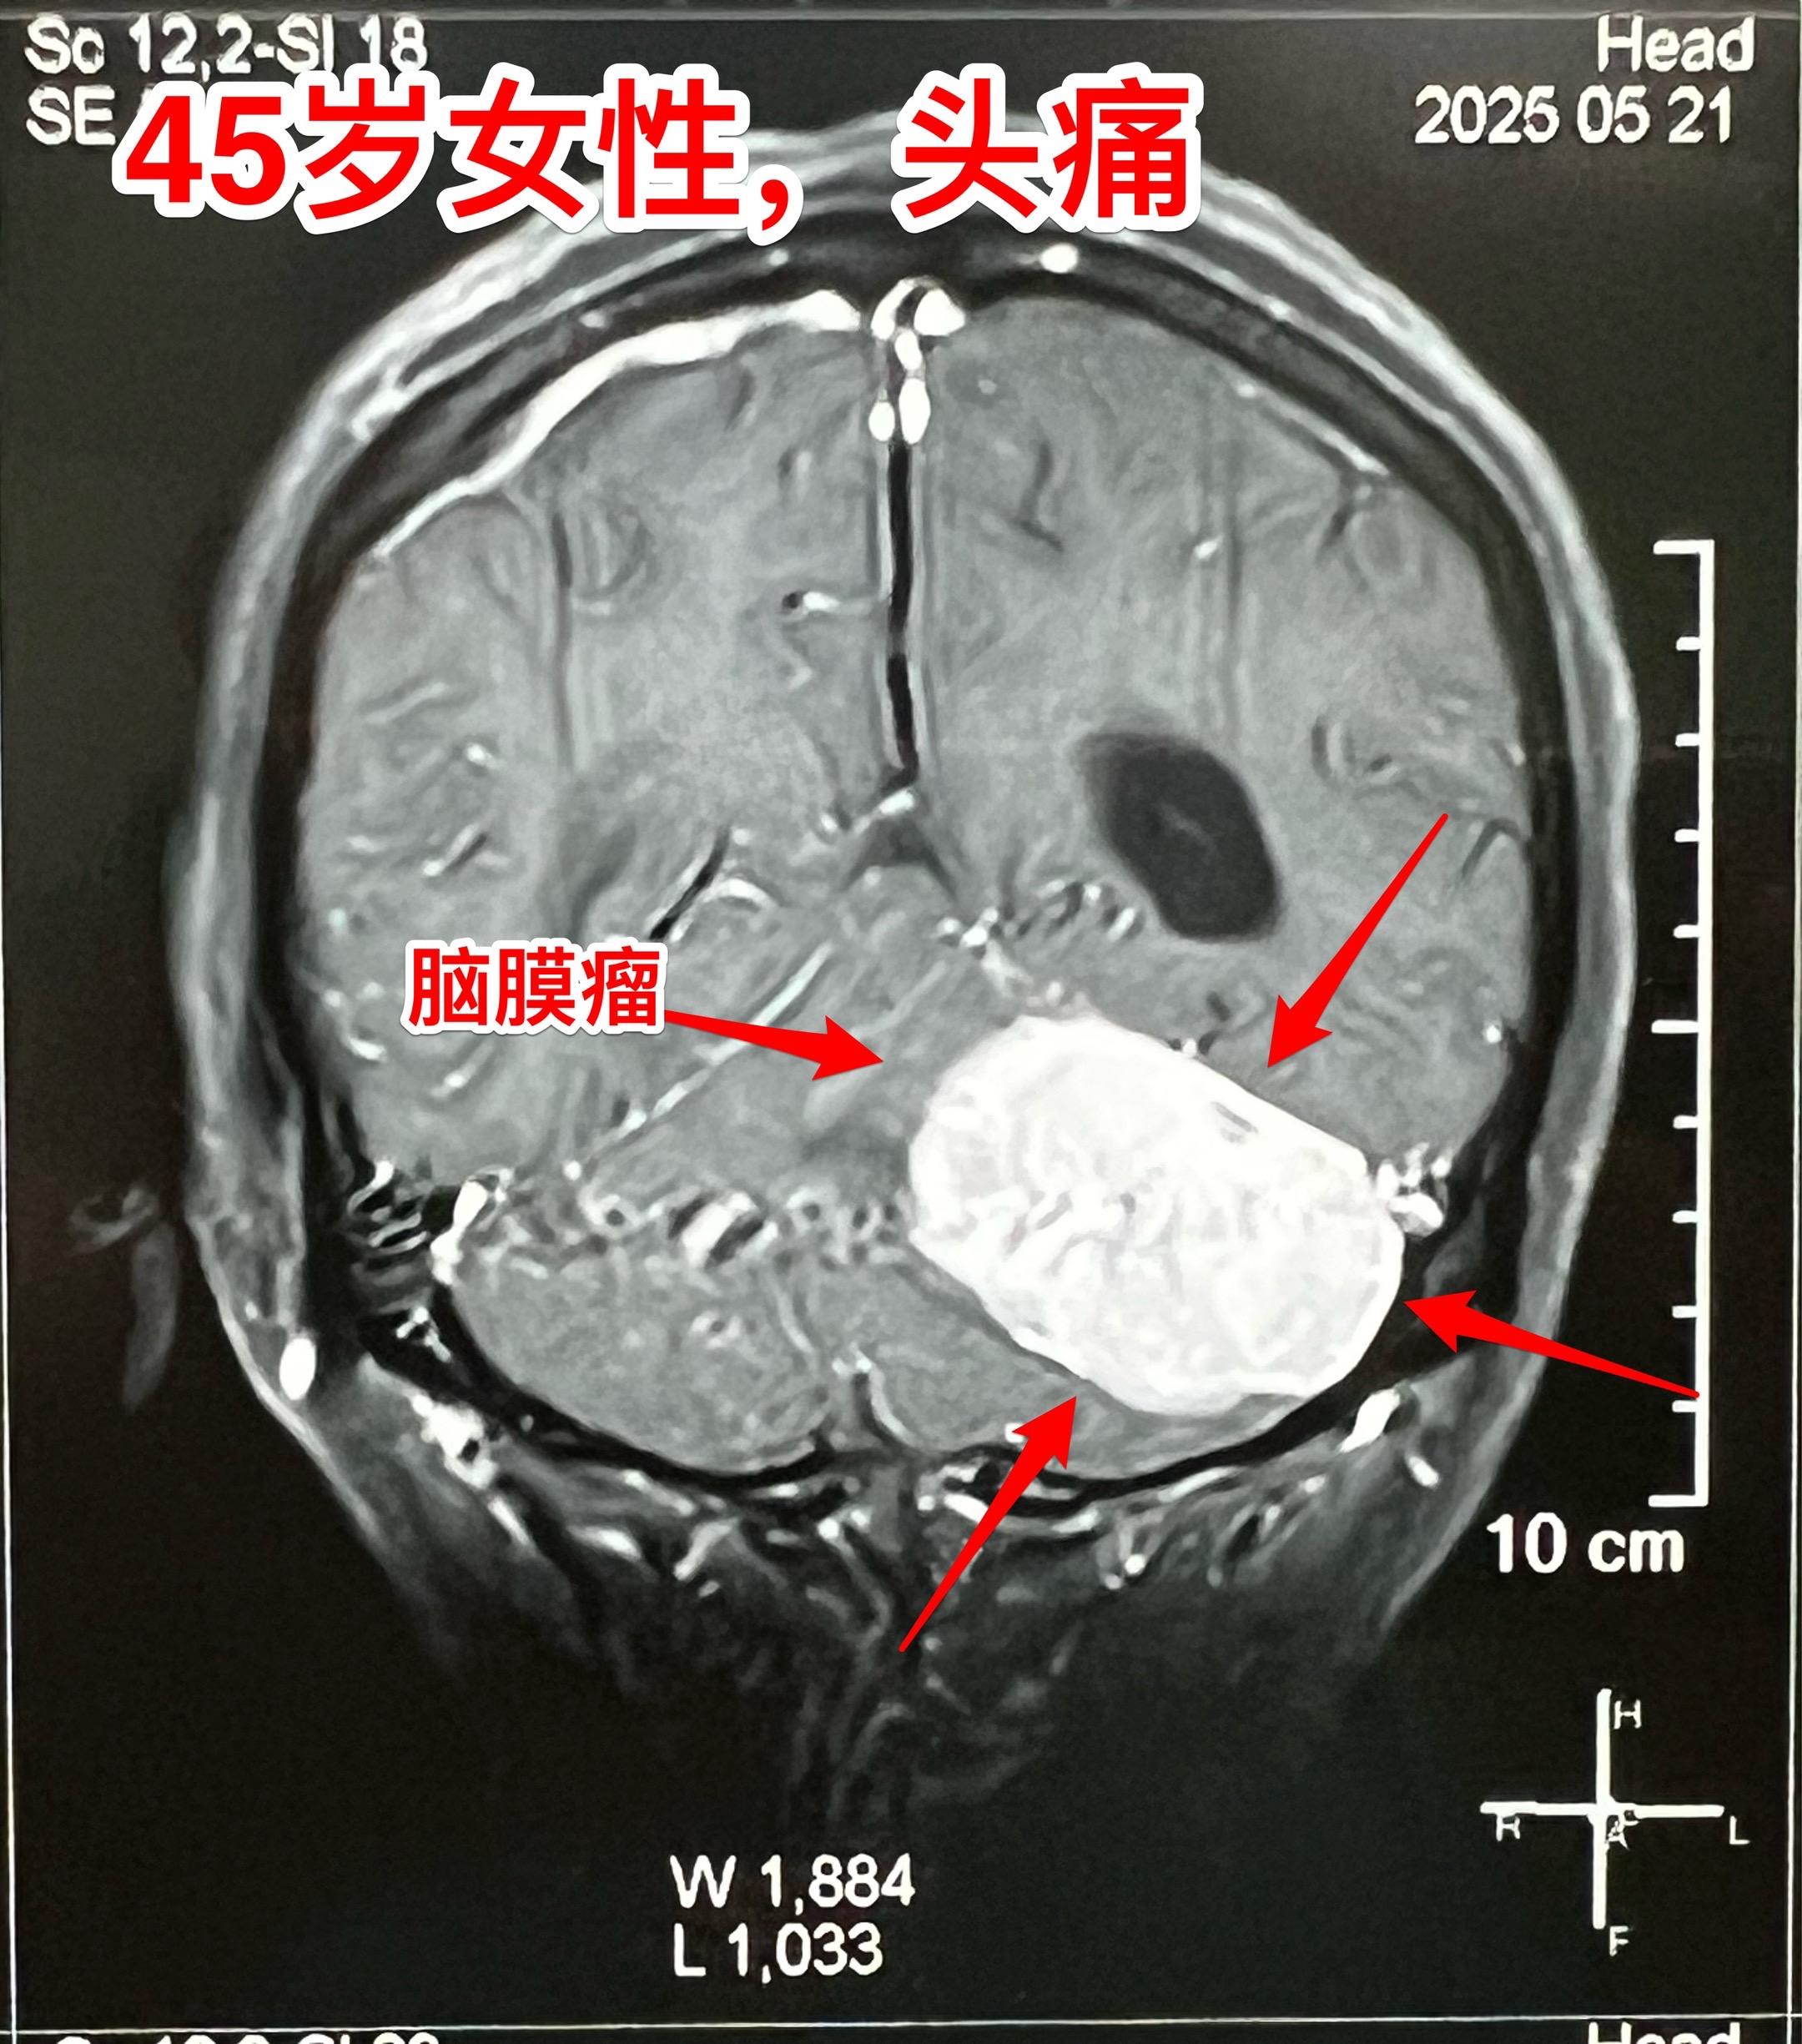

45岁女性因头痛发现脑膜瘤。45岁呼伦贝尔女性,在北京工作。头痛症状不剧烈,无呕吐。到医院就医,作头部CT检查发现可疑问题,再作磁共振检查发现左侧小脑表面有个巨大的脑膜瘤,伴有脑积水。 5月23日作了手术(只能是开颅手术)将脑膜瘤完全切除。 这样的脑膜瘤属于相对浅表位置的肿瘤,比颅咽管瘤手术要容易的多。脑膜瘤虽然是良性肿瘤,也有一定的复发率。